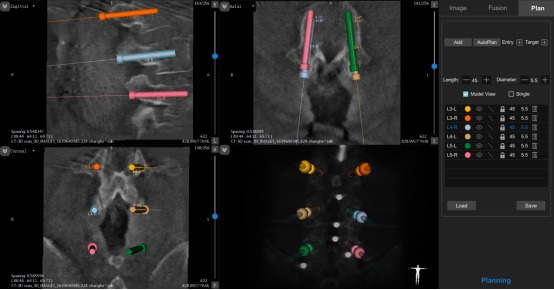

此外,术者根据置钉规划在机械臂轴向深度约束下通过高速磨钻建立椎弓根骨性通道(图3、4),随即置入实心椎弓根螺钉。

图3 椎弓根螺钉规划示意图

图4 机器人辅助建立椎弓根通道